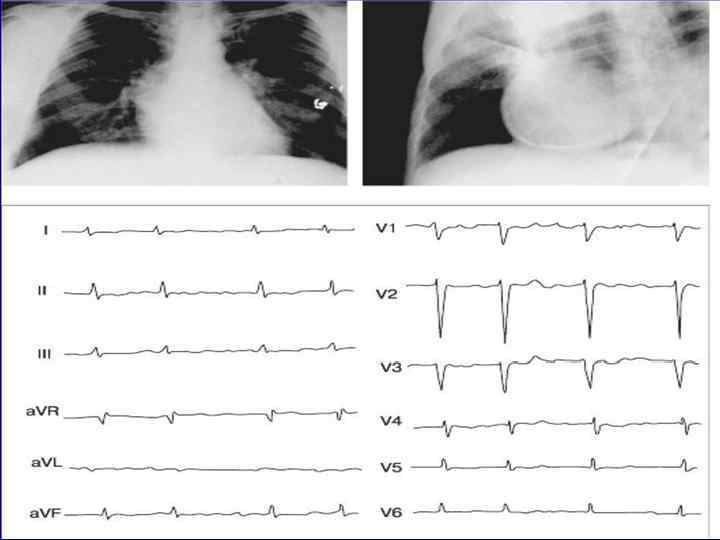

ЭКГ при сухом перикардите • Изменения на ЭКГ при остром перикардите проходят 4 стадии: • 1 стадия: в начале заболевания отмечается подъем сегмента ST в большинстве отведений • 2 стадия: примерно через неделю сегмент ST возвращается на изолинию • 3 стадия: формируется распространенная инверсия зубца Т в тех же отведениях, сохраняющаяся в течение нескольких месяцев после выздоровления • 4 стадия: происходит возврат показателей ЭКГ к исходному уровню

• Указанные изменения ЭКГ отражают субэпикардиальную ишемию вследствие вовлечения в воспалительный процесс поверхностных слоев миокарда. • Правильная терапия может предотвратить появление всех четырех стадий. • Изменения, характерные для 1 стадии, отмечаются более чем у 80% пациентов с перикардитом

• Конкордантное (однонаправленное) смещение сегмента ST выше изоэлектрической линии во многих ЭКГ отведениях • Отсутствие патологического зубца Q • Изменение формы и полярности (инверсия) зубца Т во многих отведениях • Появление синусовой тахикардии • Различные нарушения ритма и проводимости • Уменьшение общего вольтажа ЭКГ (при появлении экссудата в полости перикарда)

ЭКГ при выпотном перикардите • Характерным ЭКГ признаком выпотного перикардита является низкий вольтаж комплекса QRS во всех отведениях, который обусловлен затуханием электрического сигнала при прохождении его через слой жидкости в полости перикарда. • Воспалительные изменения субэпикардиального слоя миокарда вызывают незначительный подъем сегмента ST от изолинии и генерализованную инверсию зубца T, так же, как и при сухом перикардите. • Реже возникают аритмии, признаки перегрузки предсердий, увеличение интервала PR.